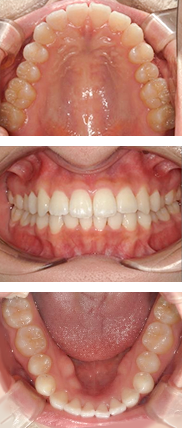

全体矯正症例

16才 女性

顎の成長が終了してから抜歯を行い、スペースを確保してそこにゆっくりと歯を移動させていきます。

歯並びも咬み合わせも整い、無事に矯正装置を外すことができました。

矯正前

矯正中

矯正後